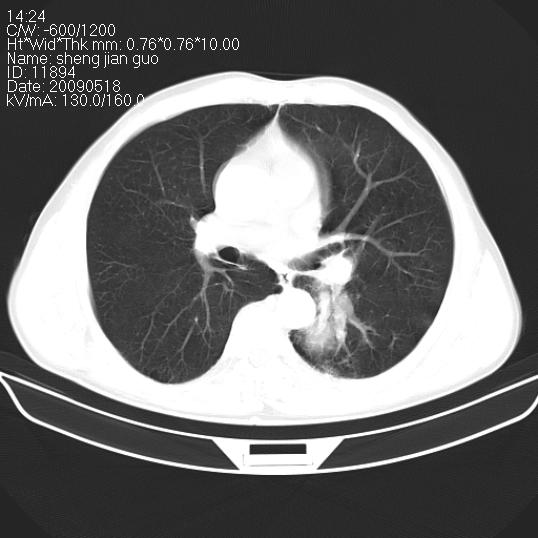

以下是引用zjzjr在2009-5-19 17:25:00的发言:[br]支持楼主考虑,另左肺下叶阻塞性炎症。

以下是引用zhao_bin2008在2009-5-19 17:48:00的发言:[br]支持左肺下叶周围型肺癌并阻塞性肺炎。

以下是引用zsl6918在2009-5-20 7:10:00的发言:[br]左侧中心型肺癌!